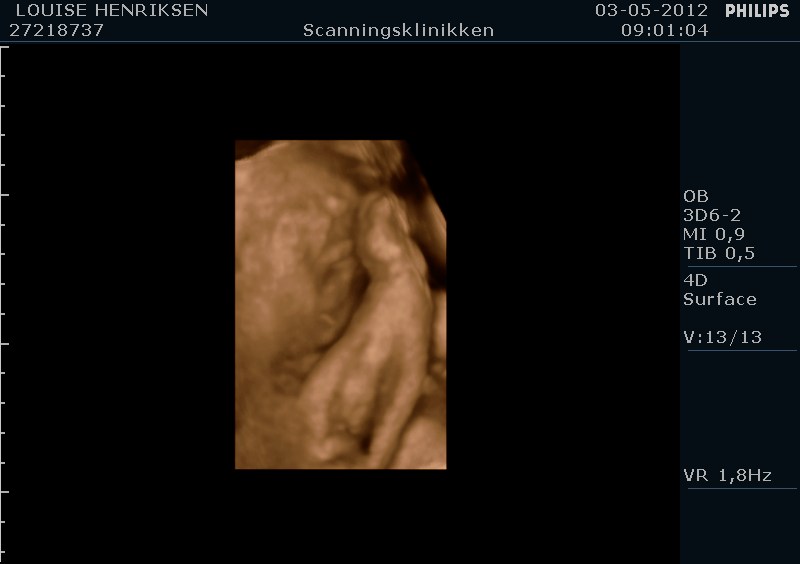

I dag skulle manden overraskes med en 4 d scanning.... og hans far var også med det var også en overraskelse, samt den lille prins....han fik bind for øjene og vi kørte mod scanning klinikken.... vi fik nogle gode sekvenser af bettemanden.. men han fylder en del derinde nu, så billederne blev ikke voldsomt gode.. men nogle fik vi dag...jeg skulle i morgen være 32 fulde uger.. mne scanningen i dag vidste34+4 dage yiarks.... jeg skal til at være færdig med den bachelor..... han vejede efter målene 1871 gram.....

så han var en fin basse...